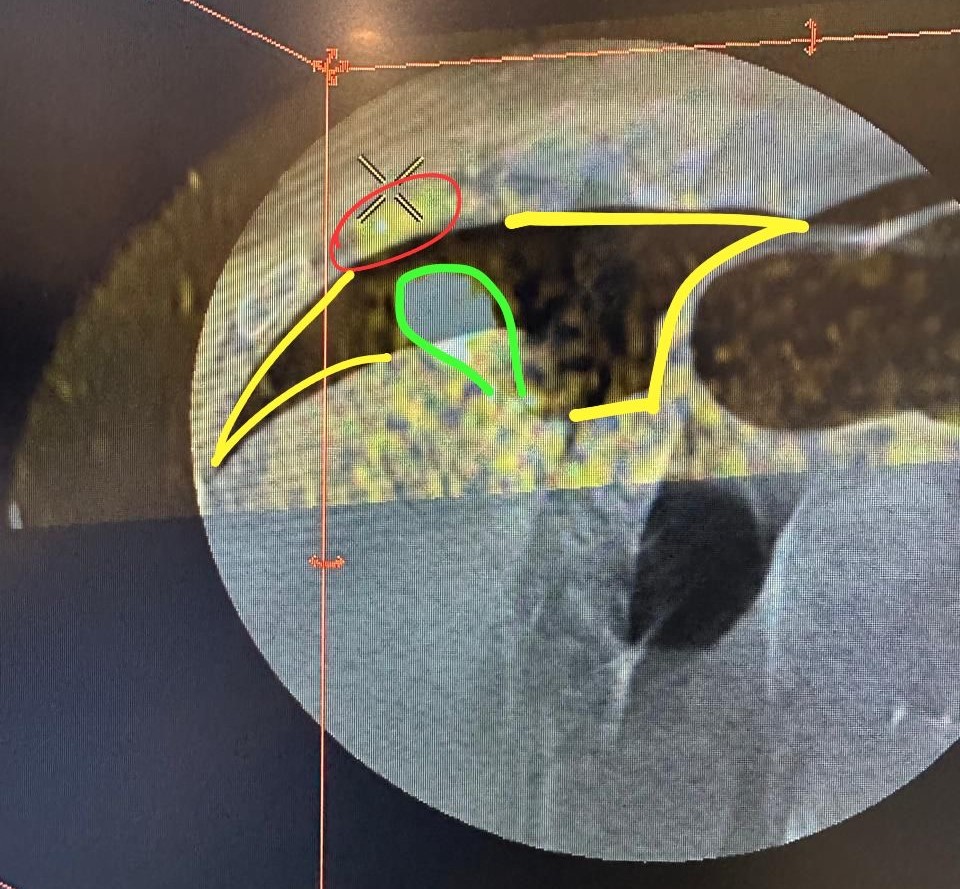

ما هو قسم الاشعة التداخلية ؟ ما هو قسم الانجيو ؟ ما الفائدة منه ؟

سأبدا في هذا الثريد اعرف عن الانجيو ببعض المعلومات وان شاء الله نفيد ونستفيد.